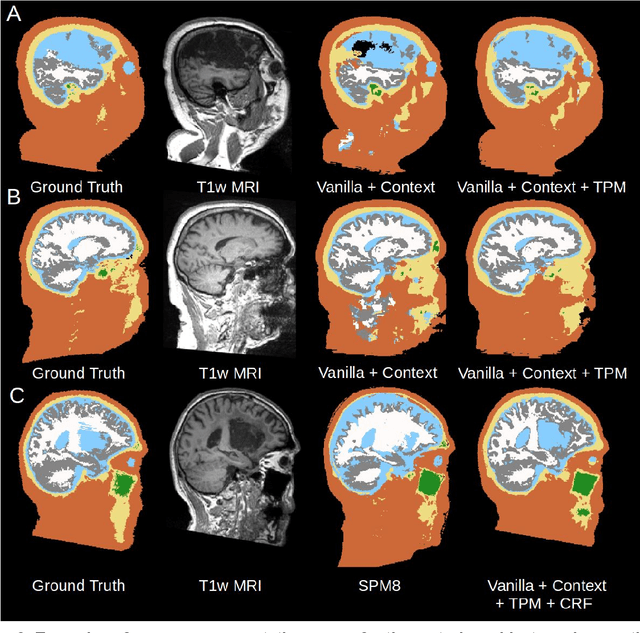

Conventional automated segmentation of the human head distinguishes different tissues based on image intensities in an MRI volume and prior tissue probability maps (TPM). This works well for normal head anatomies, but fails in the presence of unexpected lesions. Deep convolutional neural networks leverage instead volumetric spatial patterns and can be trained to segment lesions, but have thus far not integrated prior probabilities. Here we add to a three-dimensional convolutional network spatial priors with a TPM, morphological priors with conditional random fields, and context with a wider field-of-view at lower resolution. The new architecture, which we call MultiPrior, was designed to be a fully-trainable, three-dimensional convolutional network. Thus, the resulting architecture represents a neural network with learnable spatial memories. When trained on a set of stroke patients and healthy subjects, MultiPrior outperforms the state-of-the-art segmentation tools such as DeepMedic and SPM segmentation. The approach is further demonstrated on patients with disorders of consciousness, where we find that cognitive state correlates positively with gray-matter volumes and negatively with the extent of ventricles. We make the code and trained networks freely available to support future clinical research projects.